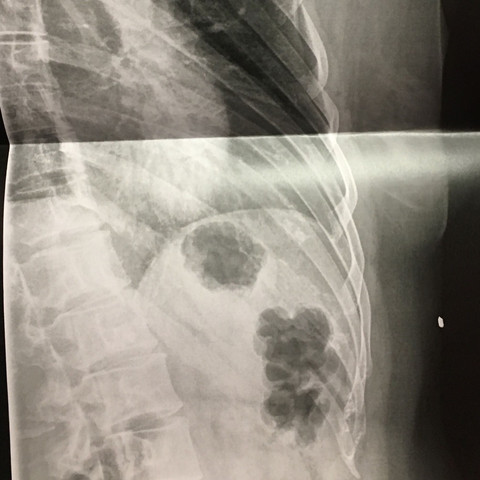

Brustkorb

Thoraxtrauma Wikipedia